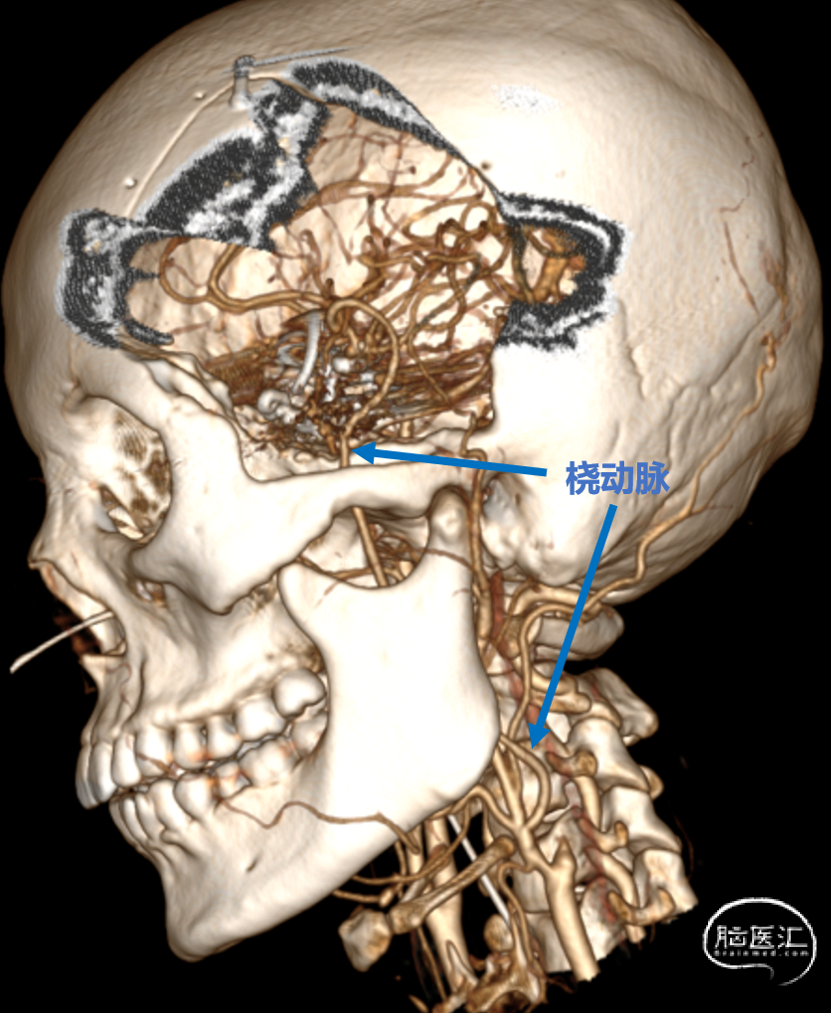

2. 术后三个月复查CTA显示动脉瘤无血流,桥血管通畅。

3.搭桥血流替代后孤立是治疗此类介入复发、血栓化巨大的动脉瘤的终极方式。只有孤立动脉瘤,使瘤体彻底的“去血化”后,结合切开减压,才能预防瘤体增大形成的占位效应。本例术前造影显示先后交通动脉开放代偿较差,故术者选择需高流量搭桥替代颈内动脉血流,保证充足脑血流灌注。下颌下隧道走行桡动脉,可缩短桡动脉所需长度,预防术后压迫。